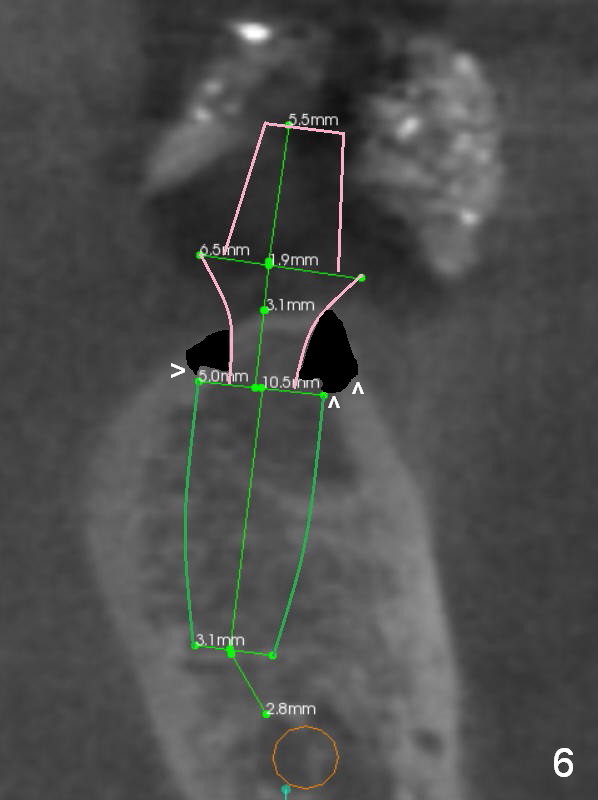

A 56-year-old man decides to have an implant at #19 after those at #13 and 14 (Fig.1 (S: CT stent)). The coronal section shows the pointed ridge (Fig.2 *). For easy implant placement and reduction in thread exposure, the ridge will be trimmed flat (Fig.3 (black area), or more exactly (funnel shaped Fig.4 (arrowheads to accommodate the shape of the cemented abutment (pink)) or concave (Fig.6)). After placing a 5x10 mm UF implant (green), bone graft to be placed (Fig.5,7 red circles) remains in place followed by collagen dressing (Fig.7 yellow lines).

Since the bone density is low (100-400 U), the last drill will be one for a 4.5 mm implant (underprep). To save the autogenous bone, reduce drill speed to 50 RPM when starting using the drill for 3.8 mm implant.